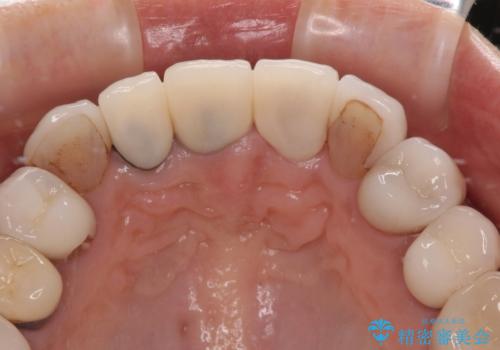

- 前歯のセラミックが欠けたり色調が不揃いであったりすることを気にして来院された患者様です。

20年以上前から、むし歯になったり詰め物が欠けたりする度に部分的に処置を行ってきたそうですが、この際統一感のある前歯にしたいとのことで、上顎前歯9本をオールセラミッククラウンによる補綴治療を行うこととしました。

色調が統一されるだけでなく、歯肉ラインに見えていた茶色の境目も綺麗に改善されました。